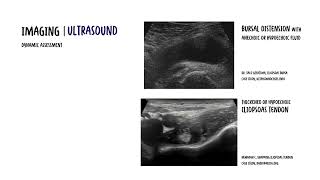

Diagnosis – Identification of bacteria in the synovial fluid.